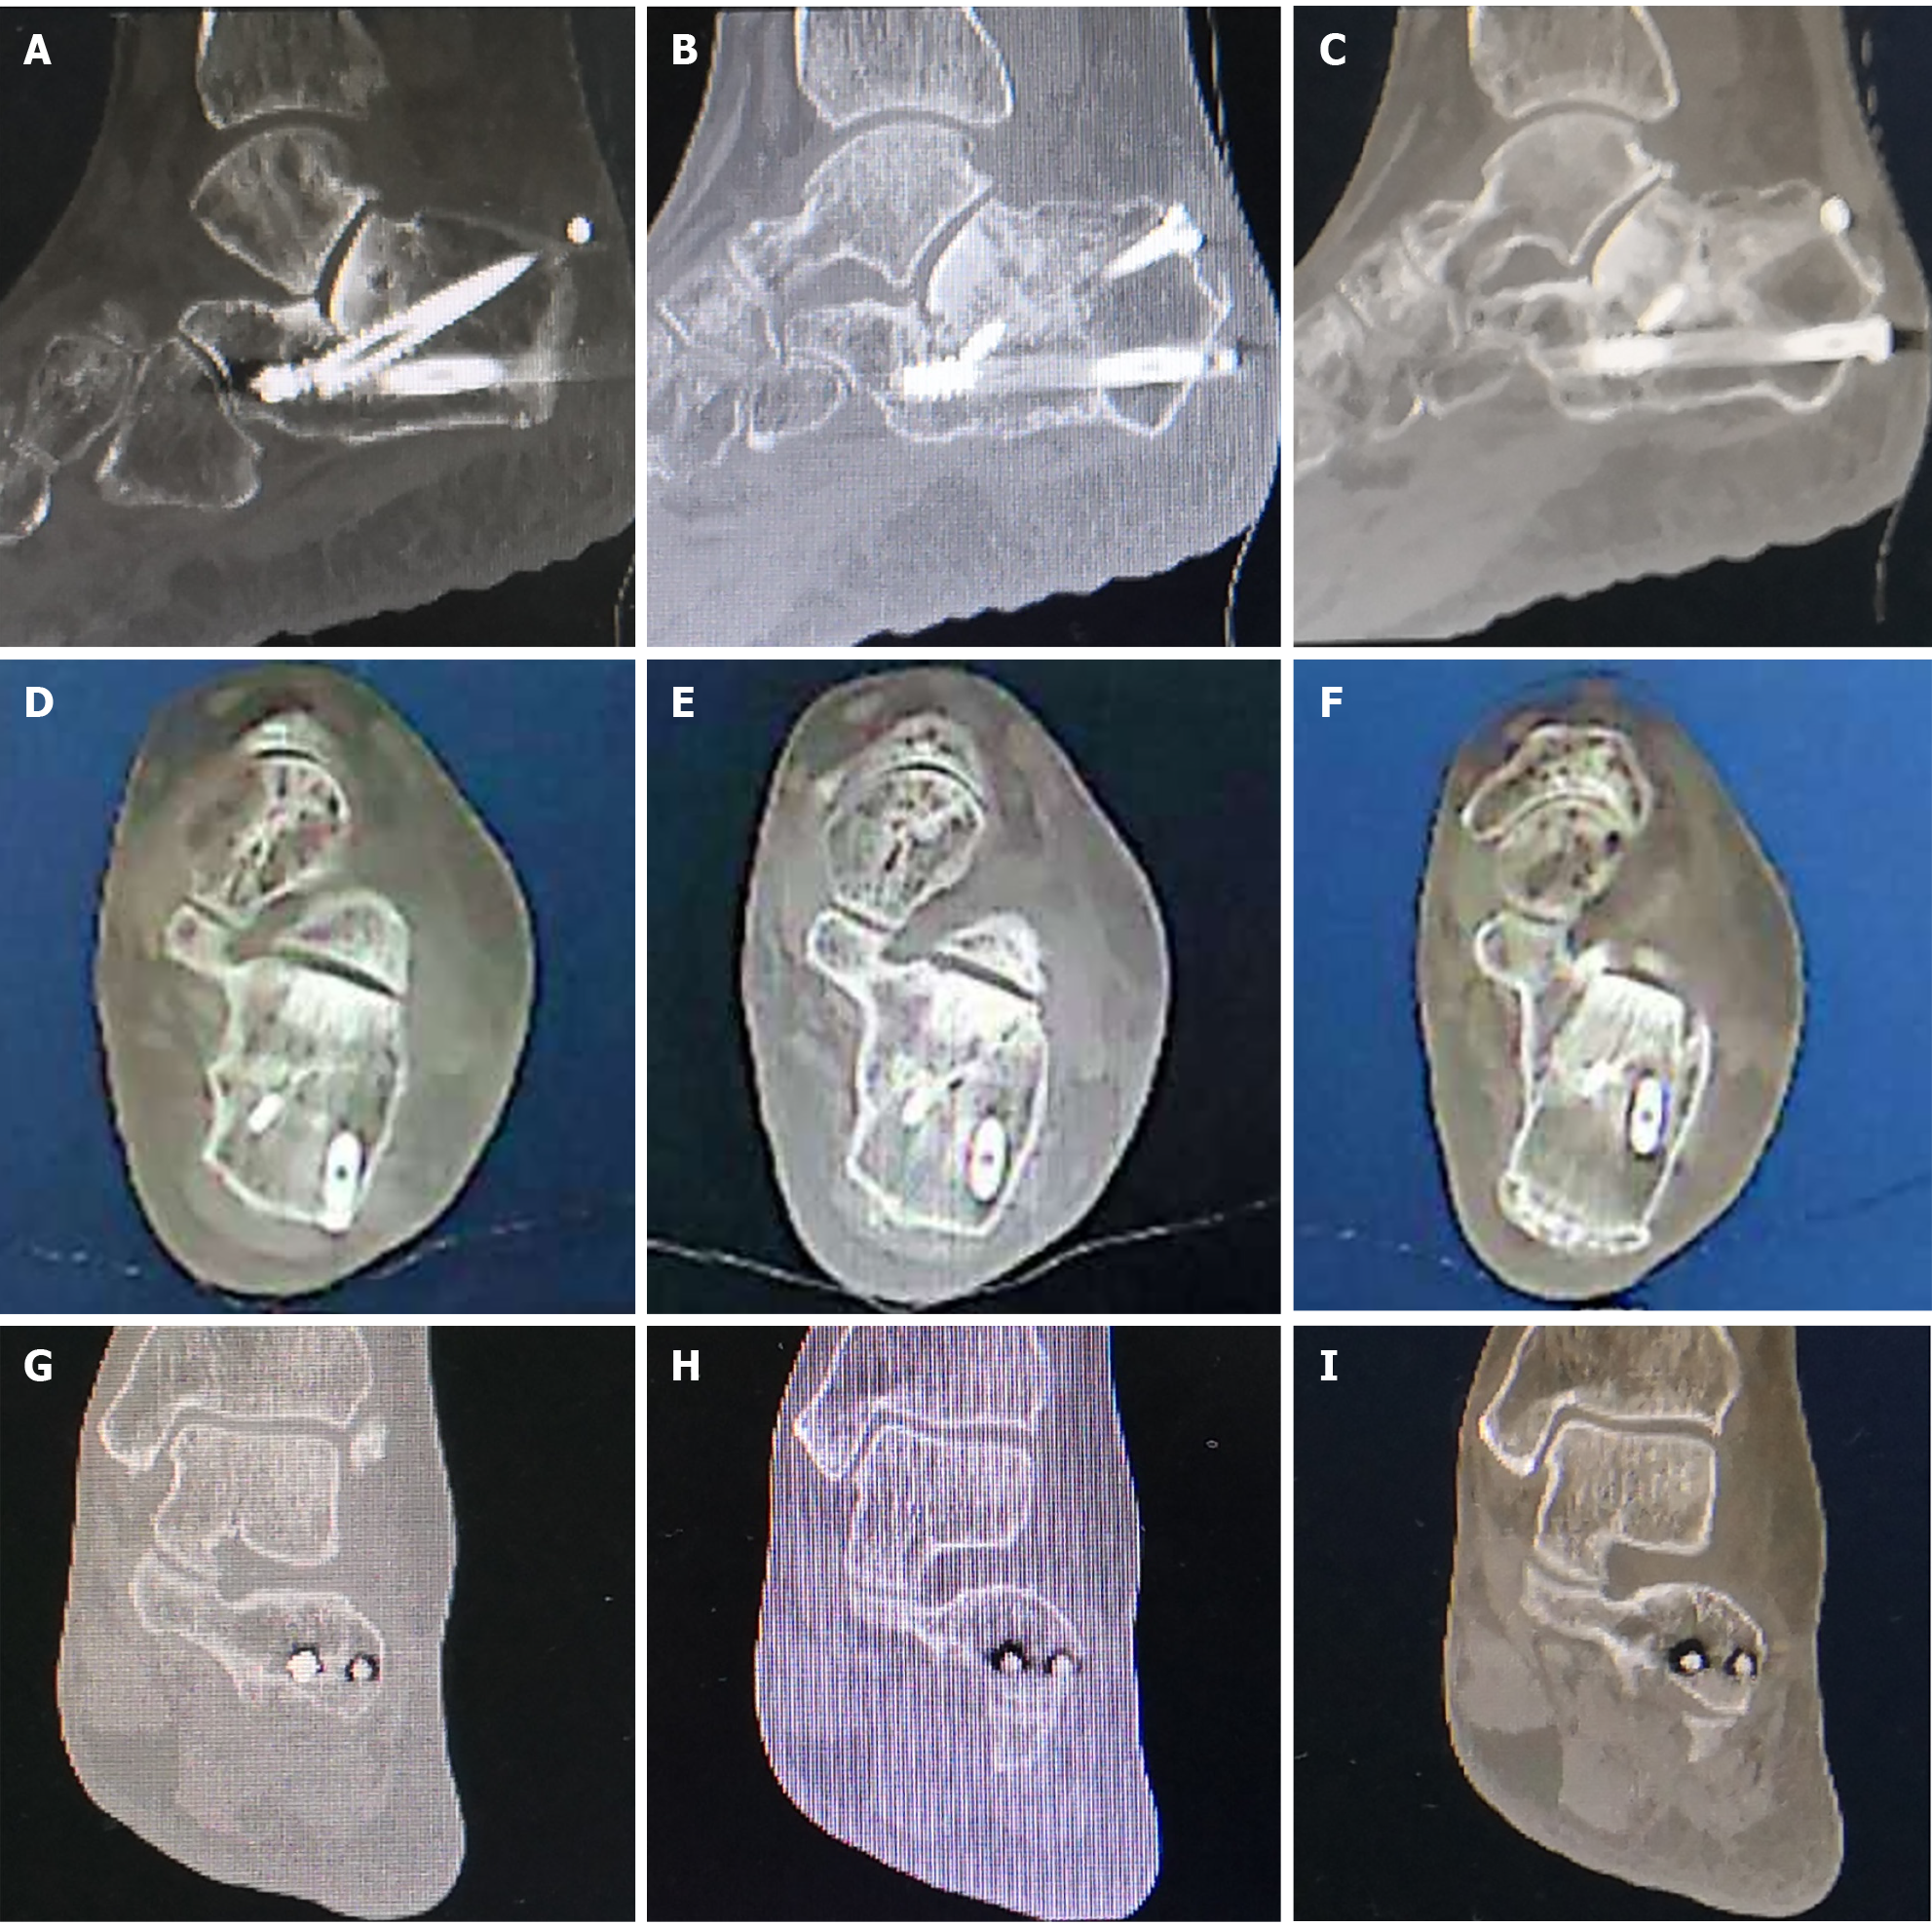

Figure 7 Seven-month postoperative computed tomography scan findings.

A-C: The Böhler’s angle was maintained at 22°; D-F: The calcaneal width was essentially restored to normal width; G-I: The subtalar joint surface demonstrated satisfactory reduction with restored articular congruity.